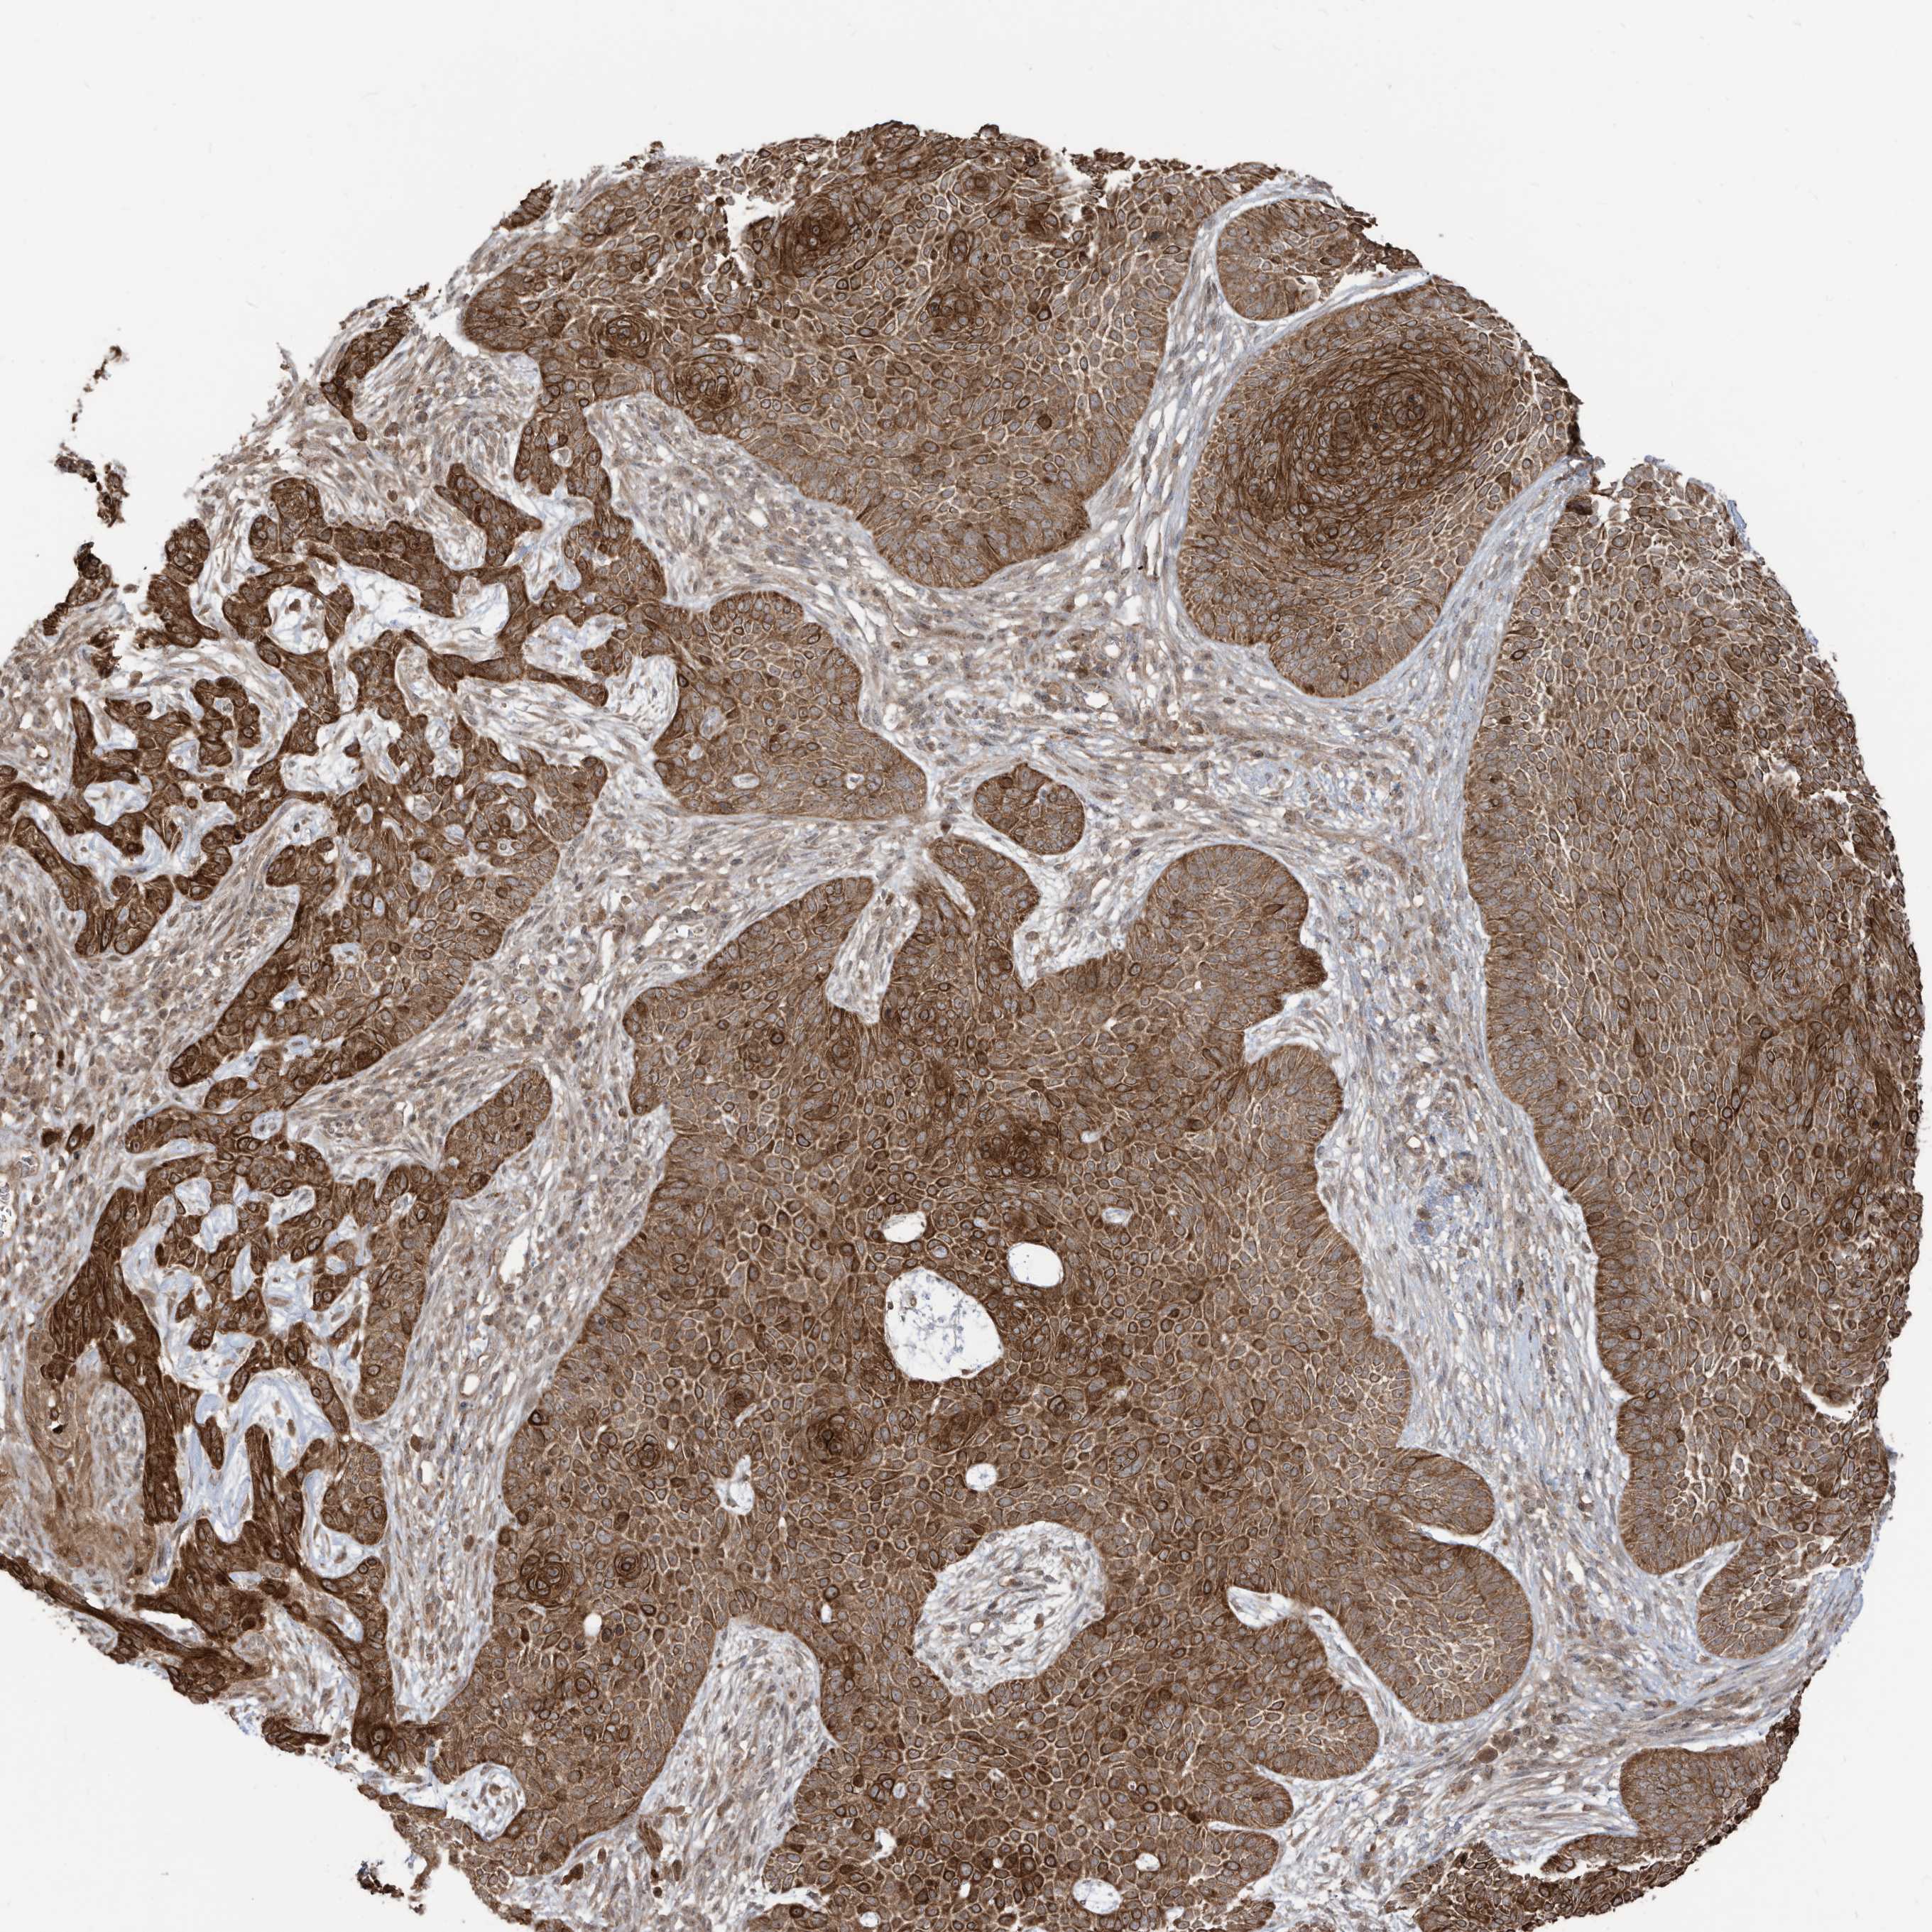

SKIN CANCER - Protein expressioni

A mouse-over function shows sample information and annotation data. Click on an image to view it in a full screen mode. Samples can be filtered based on level of antibody staining by selecting one or several of the following categories: high, medium, low and not detected. The assay and annotation is described here.

Antibody stainingi

Antibody staining in the annotated cell types in the current human tissue is reported as not detected, low, medium, or high, based on conventional immunohistochemistry profiling in selected tissues. This score is based on the combination of the staining intensity and fraction of stained cells.

Each image is clickable and will lead to virtual microscopy that enables deeper exploration of all samples and also displays staining intensity scores, fraction scores and subcellular localization as well as patient and tissue information for each sample.

Antibody HPA034557

Staining

High

Medium

Low

Not detected

Intensity

Strong

Moderate

Weak

Negative

Quantity

>75%

75%-25%

<25%

None

Location

Nuclear

Cytoplasmic/membranous

Cytoplasmic/membranous,nuclear

Basal cell carcinoma